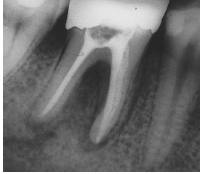

Radiografía final del tratamiento endodóntico

Control radiográfico a los 18 años